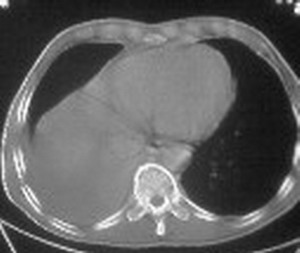

ct值约12hu。

ct值约12hu

右肺下叶支气管阻塞,右下叶不张,考虑中心型肺癌伴下叶不张

先考虑:右下肺中心型肺癌伴下叶肺不张、胸腔积液

右肺下叶支气管闭塞,中间段支气管狭窄,下叶不张,胸腔及叶间积液.中心型肺癌伴下叶肺不张.胸腔和叶间积液.

右肺下野后部均匀低密度影,边缘锐利,前缘外突(不支持肺不张),纵隔内未见明显肿大淋巴结,右下肺门结构显示欠清,临床资料太过简单,考虑右侧后胸部包裹性积液。其他待排。建议密切结合临床其他检查。